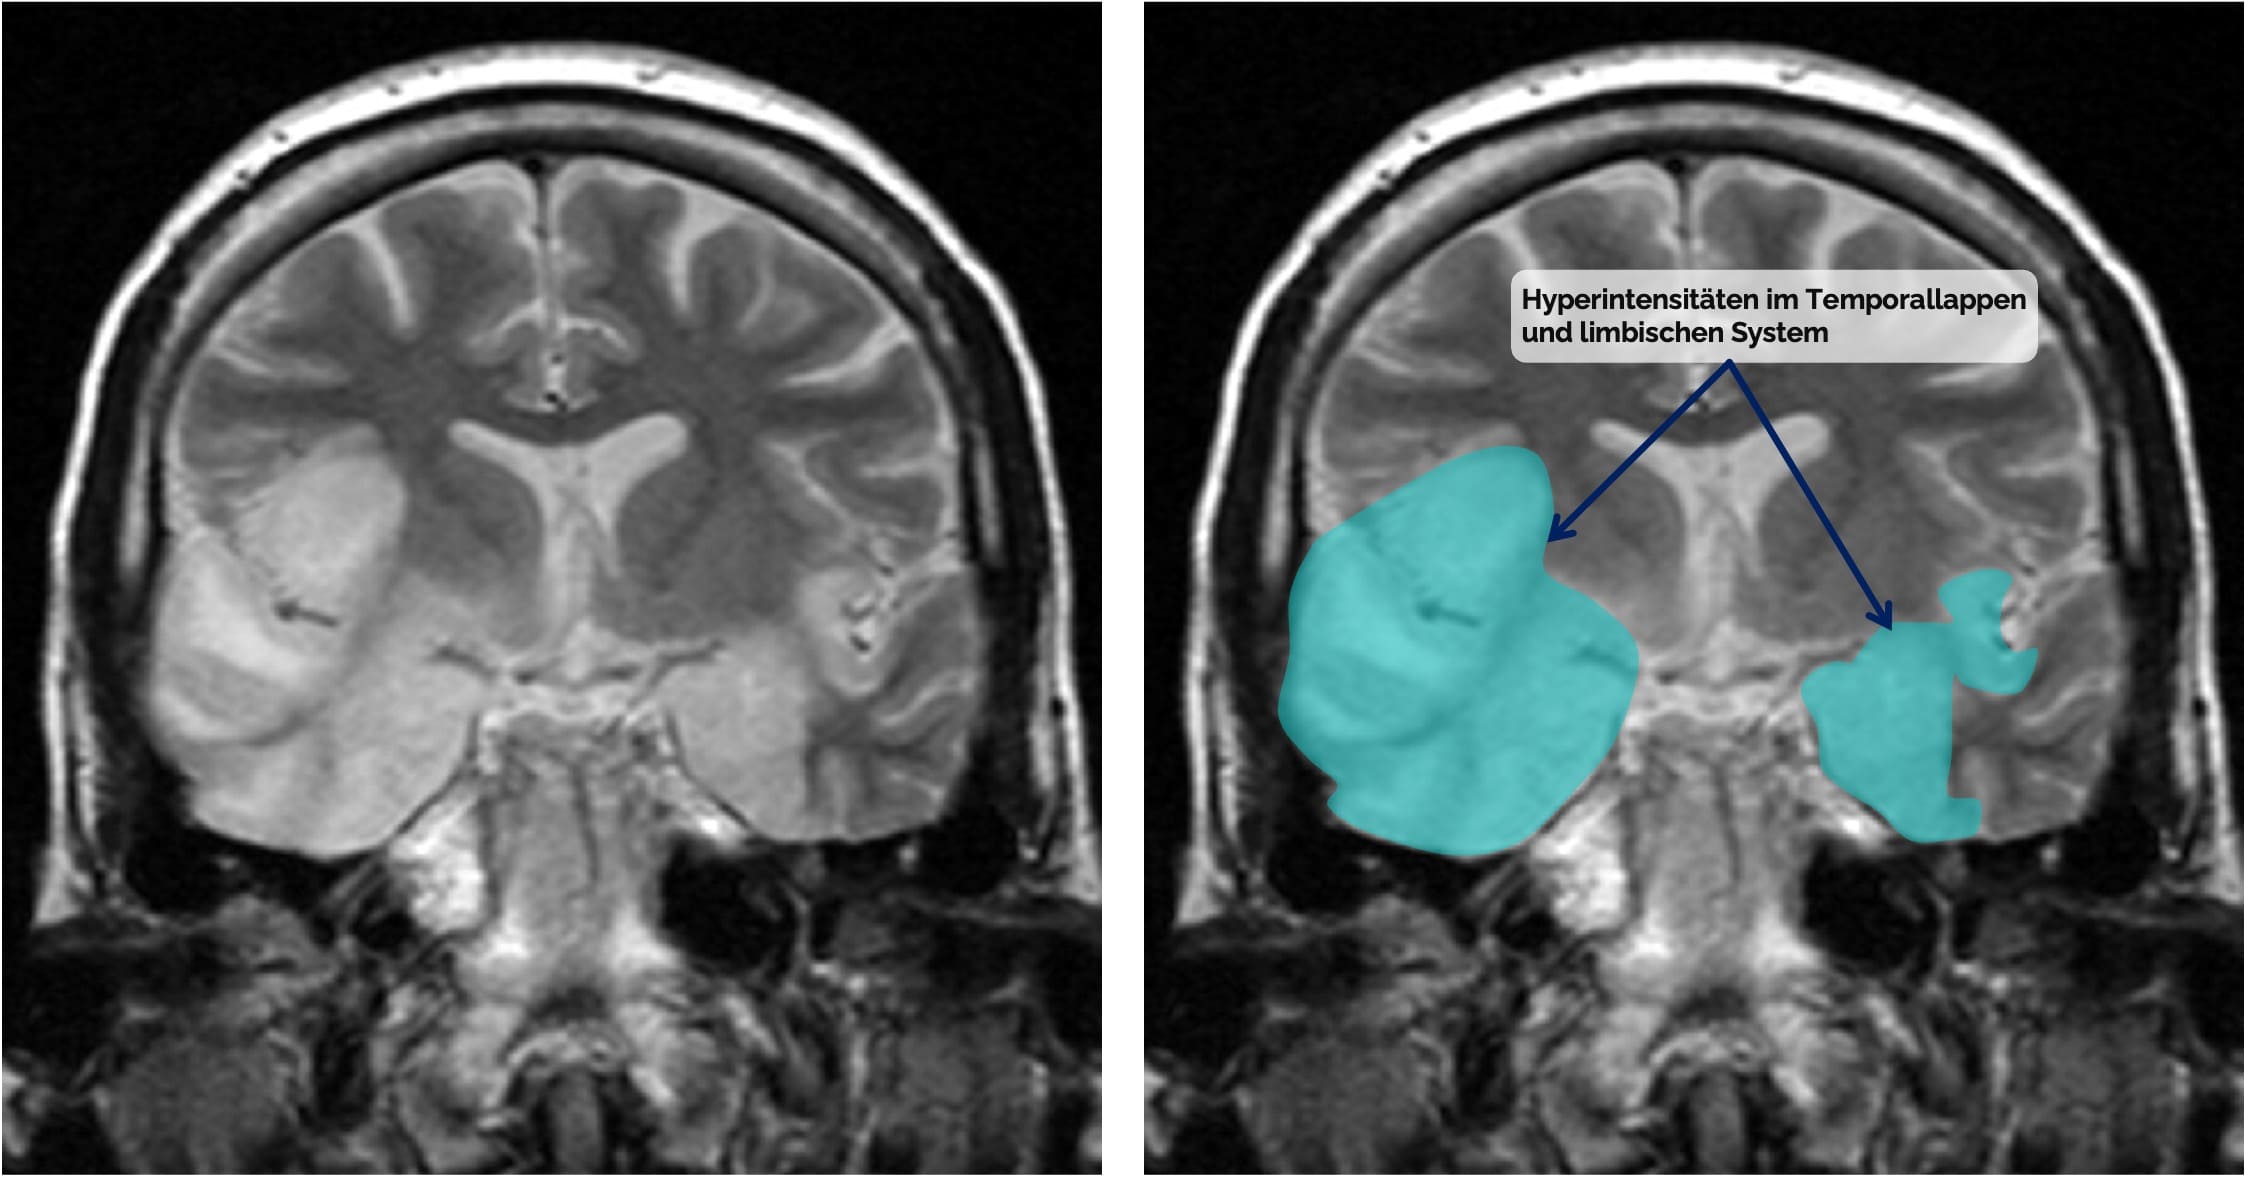

Meist unilaterale Läsionen im mesialen Temporallappen und limbischen System, z.T. hämorrhagisch

Erregerspezifische Hinweise im cMRT

Eine Herpes-simplex-Enzephalitis zeigt typischerweise unilateral-betonte T2/FLAIR-Hyperintensitäten im mesialen Temporallappen und limbischen System, teils mit hämorrhagischen Anteilen. Bei tuberkulöser Meningitis finden sich oft kontrastmittelanreichernde Veränderungen in den basalen Zisternen, kombiniert mit Hydrozephalus und ischämischen Infarkten durch entzündliche Gefäßbeteiligung. Eine Kryptokokkenmeningitis kann insbesondere bei immunsupprimierten Patient:innen gelatinöse Pseudozysten in den Basalganglien hervorrufen. Die zerebrale Toxoplasmose weist typischerweise multiple ringförmig kontrastmittelanreichernde Läsionen mit perifokalem Ödem in Basalganglien und kortikomedullären Übergängen auf. VZV und invasive Mykosen wie Aspergillosen gehen häufig mit multiplen Infarkten oder hämorrhagischen Läsionen einher, bedingt durch vaskulitische oder angioinvasive Prozesse.

Befall des Temporallappens und des limbischen Systems bei HSV-Enzephalitis